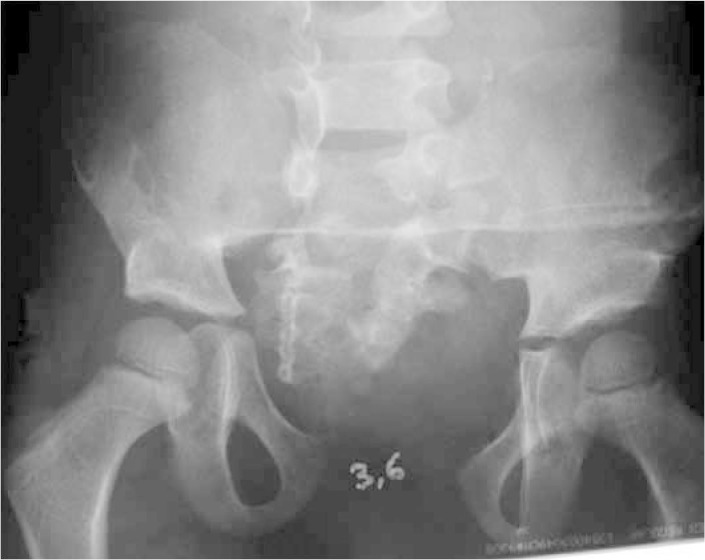

The first patient was five months old and was referred to a pediatric surgery service with a diagnosis of bladder exstrophy, presenting preoperative pubic diastasis of 4.2 cm (Figure 3)

Figure 3.

Preoperative radiograph on patient with bladder exstrophy, showing pubic diastasis of 4.2 cm.

This patient underwent bilateral anterior pelvic osteotomy, performed by the present author in June 2005, using the technique subsequently described, concomitantly with bladder closure performed by the pediatric urological surgery team, at the age of five months. The procedure was made more difficult because of a lack of image intensifier during the surgical procedure, which made pin placement somewhat more laborious, with the need to produce intraoperative radiographs in order to verify that their positioning was correct (Figure 4A). Reduction of the diastasis to 2 cm was achieved in the immediate postoperative period (Figure 4B)

Figure 4.

A) Left: patient at the end of the orthopedic procedure, released to undergo bladder closure. B) Right: radiographic appearance during immediate postoperative period.

The patient remained in hospital for one week and no traction was used; only resting in bed. An external fixator was used for a total of eight weeks, and no type of complication was presented. Two years after the surgery, it was found that the patient had lost some of the reduction, but the result remained satisfactory, with diastasis of 3.8 cm and good urological function (Figure 5). In the late postoperative period, the patient was already walking, with gait on a normal base, and no external rotation of the legs was presented. There was no recurrence of or complication from the urological abnormalities

Figure 5.

A) Left: pelvic radiograph one year after the operation, showing diastasis of 3.8 cm. B) Right: appearance of closed bladder two years after the operation.